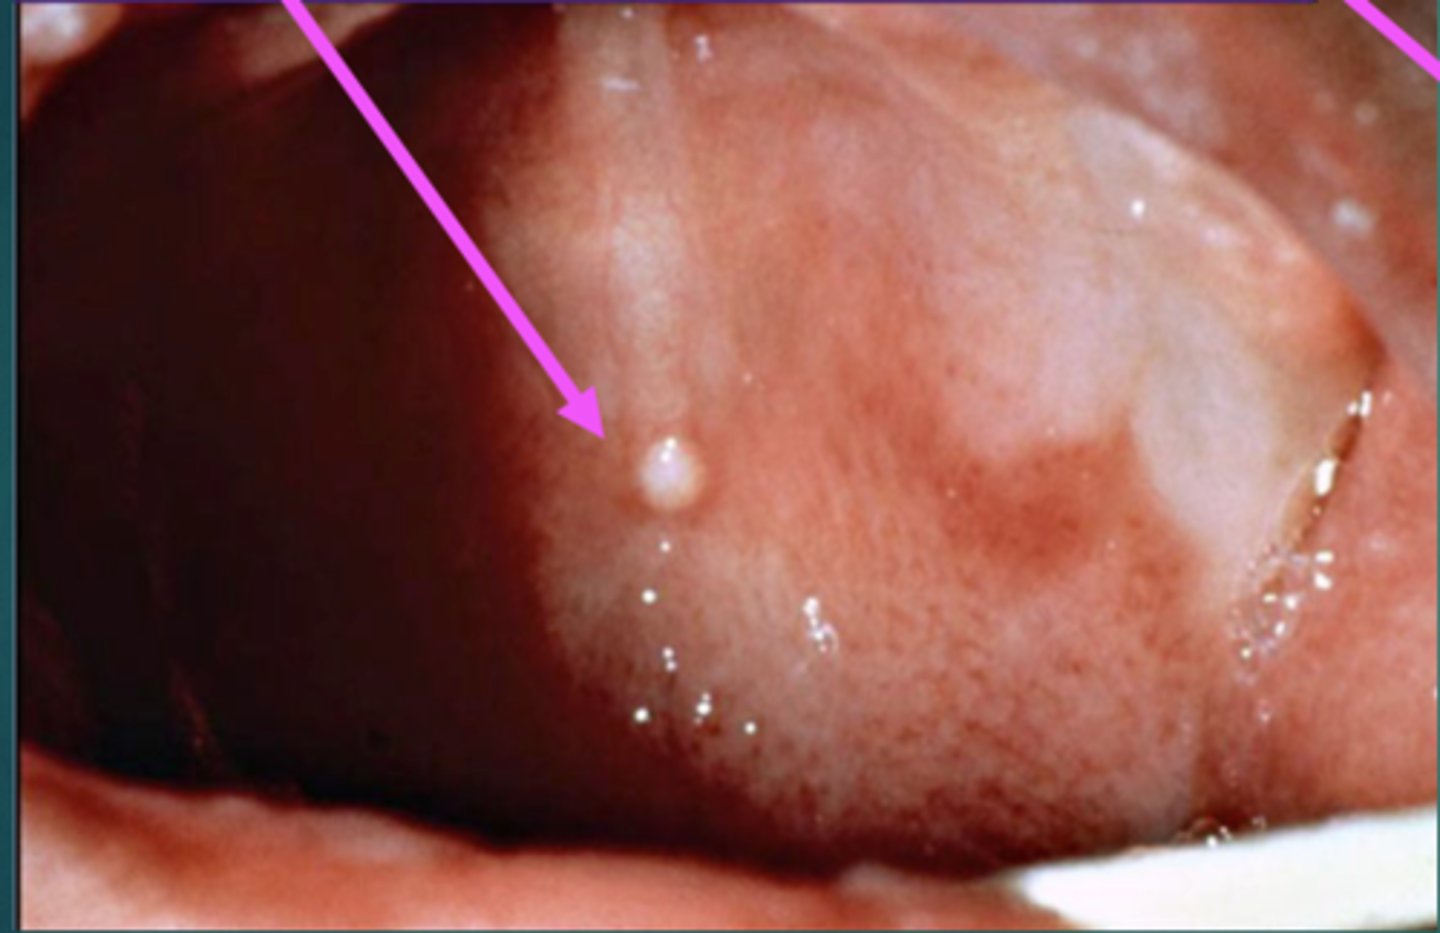

Define inclusion cysts.

Also called EPSTEIN'S PEARLS. Small, harmless, white or yellow NODULES that may appear along the newborn's GUMS or on the ROOF of their mouths. These are COMMON.